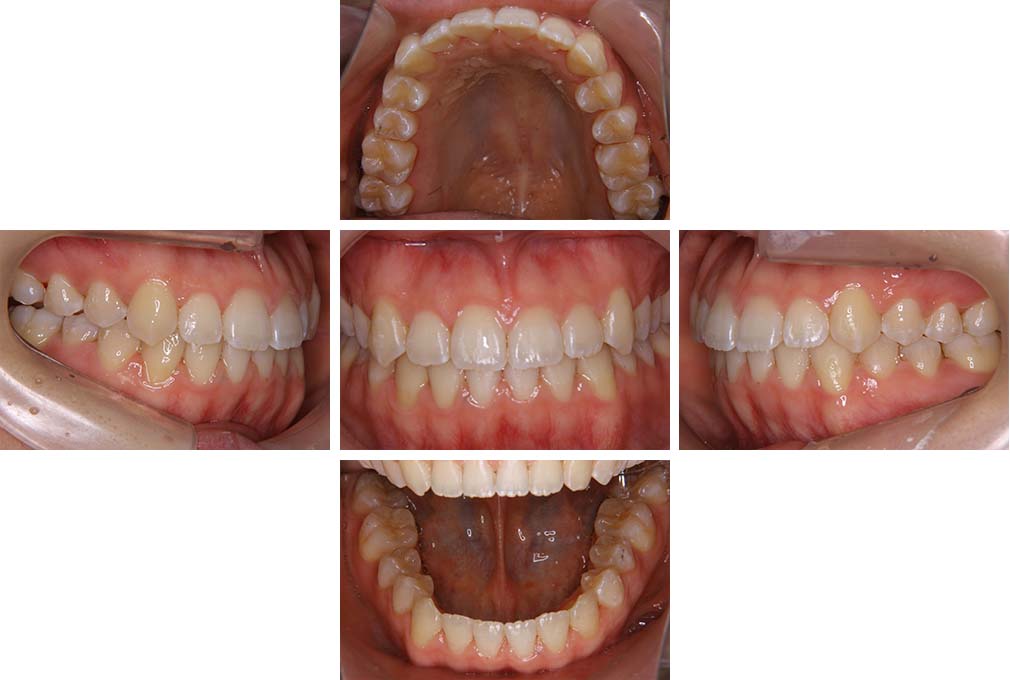

CASE:03

上下顎前突

初診時年齢 18歳4か月

性別 男性

治療費の目安 105万円程度(治療開始時)

歯列の乱れは著しくなく上顎右側側切歯が捻転し口蓋側へ転位していた。また、問診の中で患者さんから最も重視する治療結果として口元の突出の改善の申出があった。下顎が後退した上顎前突傾向ではあったが著しいものではなかった。上下顎前突と診断し上下顎小臼歯抜歯を行っていただき、上下顎舌側マルチブラケット装置を使用して、矯正用アンカースクリューを併用して動的治療を行った。上下顎前歯の後退を十分行い口元の突出感も改善した。治療後10年1か月の来院時には口元の突出感が再発することもなく、下顎前歯の少しの唇舌的なずれはあったが歯列は安定していた。動的治療期間2年2ヵ月間。

治療前

18歳4ヵ月

治療後

動的治療期間2年2カ月間

20歳10か月

10年経過

動的治療終了後10年1カ月

30歳11か月